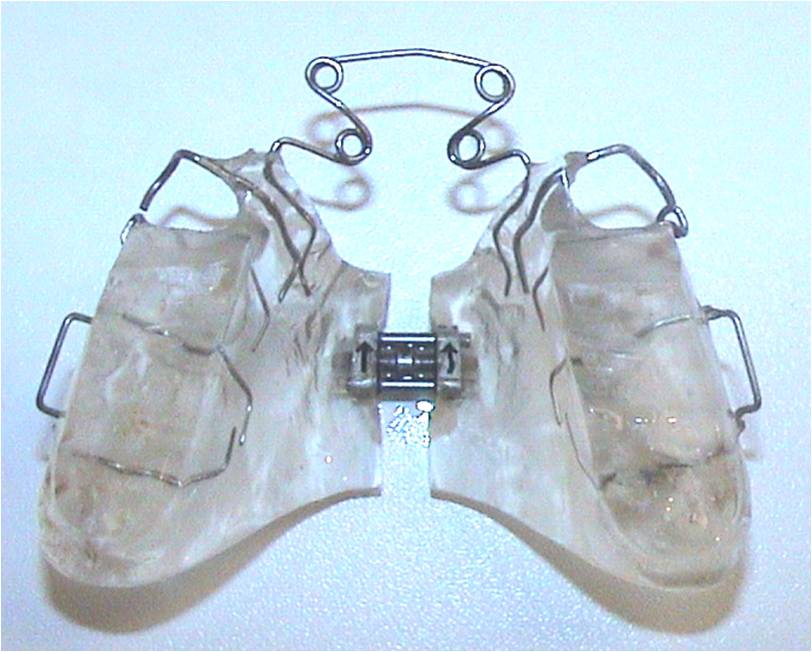

Twin-Block-Apparatur mit frontaler Quad-Helix

Nach Prof. Dr. Polzar (KKU) modifizierte Twin-Block-Apparatur mit frontaler Quad-Helix zur Protrusion der OK Frontzähne und mit Schrauben zur transversalen Nachentwicklung.